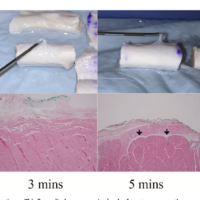

この論文の中心テーマは、ECU腱不安定症に対する手術法です。内容を簡単にまとめると、手術では主に破れたsubsheathの修復、あるいは伸筋支帯を使った再建が行われます。

論文では、解剖学的修復と非解剖学的再建の両方が紹介されていますが、伸筋支帯の一部を用いた再建は広く行われ、良好な成績が報告されているとされています。

また、手術中にはECU腱そのものの状態も確認し、腱鞘炎、縦断裂、変性があれば同時に処置します。部分断裂が軽度なら修復、広範なら腱移植再建が必要となることもあります。